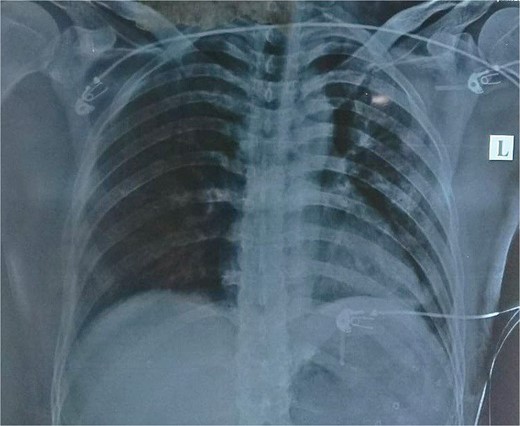

Routine examinations, including total blood counts, differential blood counts, renal function tests, and liver function tests, were within normal limits. The chest X-ray PA view showed the herniation of bowel loops into the left hemithorax with the collapse of the lower zone of the lung with no evidence of previous fracture (Fig. 1). Computed tomography (CT) showed a defect of size around 4 cm with evidence of protrusion of intra-abdominal content in the left hemidiaphragm with basal atelectasis of the left lung and mild dilatation of the jejunal bowel loops with a few air-fluid levels without a transition point (Fig. 2). The patient underwent laparoscopic left diaphragmatic hernia repair with mesh hernioplasty after 6 h of admission. The intraoperative findings revealed a defect of size 4 cm × 2 cm at the posterolateral aspect of the left hemidiaphragm with protrusion of the transverse colon, omentum, and part of the spleen with adhesions (Fig. 3). The content of the hernia was reduced, and primary repair of the defect was done (Fig. 4), and the defect was closed with a 10 × 15 cm intraperitoneal onlay composite mesh (Fig. 5). A postoperative X-ray showed no evidence of herniation of the bowel loops above the left hemidiaphragm (Fig. 6). He was discharged on the fourth postoperative day with oral medications. Follow-up in the outpatient department on the 14th postoperative day showed that he was doing well.

Chest X-ray PA view showing the herniation of bowel loops into the left hemithorax with collapse of the lower zone of the lung.